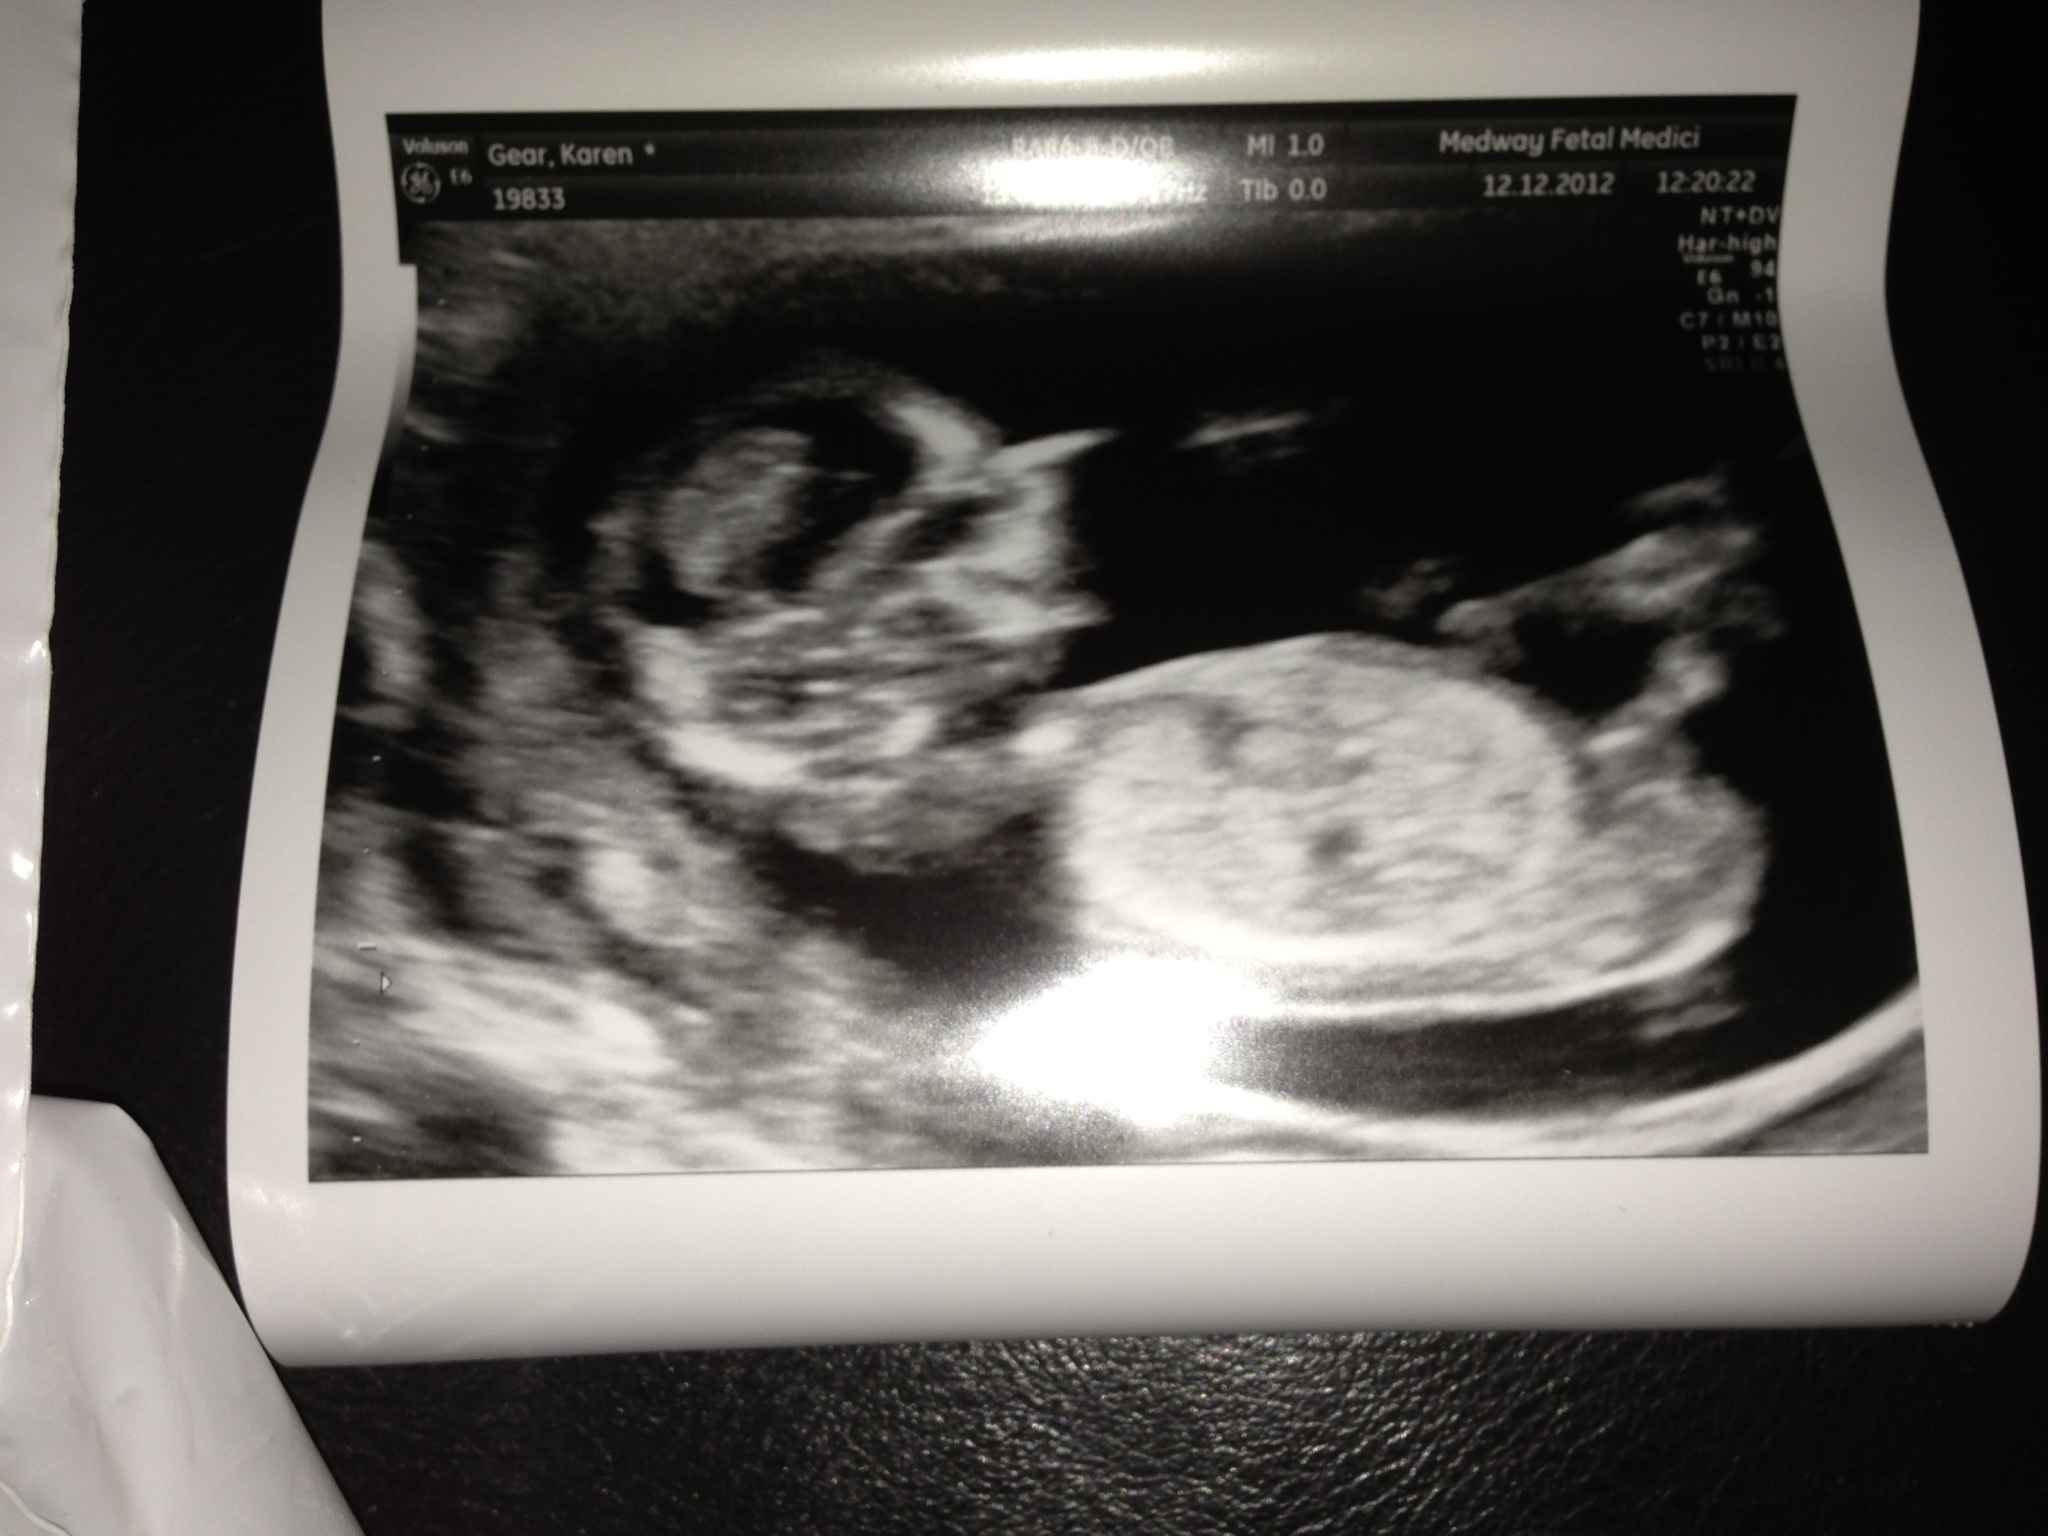

Hi I posted my us pics and have studied my previous children's pics and the nub on theirs looks defined which makes me think this is not a nub - can anyone explain what it is though in the nub area? Sorry to be a pain but struggling a bit at mo. thanks for looking and helping ...

Attachment 7289Attachment 7290